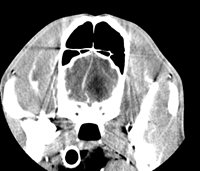

Encephalon

- Exploration of Epileptic Seizures and Convulsive Syndromes

- Exploring Stroke

- Head injuries

- Exploration of pituitary Cushing's syndromes

- Amaurosis (loss of sight)

- Suspension of congenital diseases: Hydrocephaly, occipital dysplasia...

- Brain tumour suspension